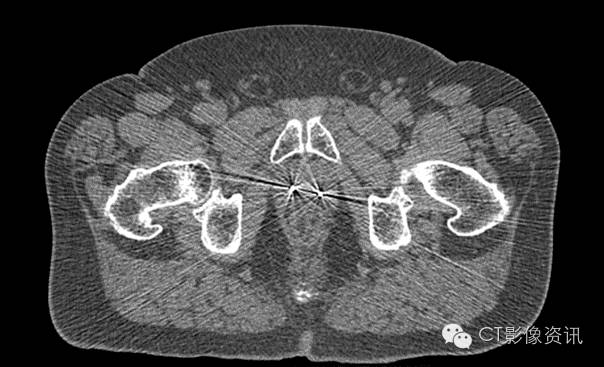

双侧髋关节置换术后

Without MAR

With MAR

Smart MAR技术可以抑制金属伪影,更清楚显示人体组织结构,更好的显示肿瘤边界,更准确的勾画肿瘤靶区,图像的CT值更准确,剂量计算更准确。